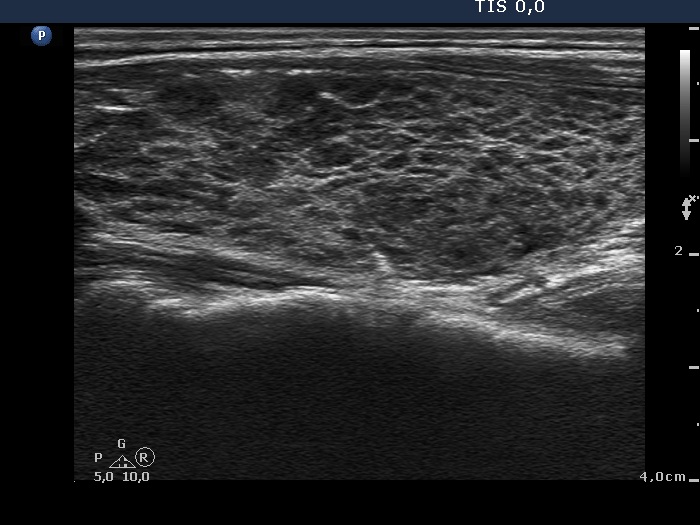

Ultrasonography: The thyroid presented the so-called honey-combing pattern: connective tissue septum divided the hypoechogenic thyroid into smaller areas.

Diagnosis: Hashimoto's thyroiditis.

Comment. It is to be avoided to overrate the relatively larger hypoechogenic areas as nodules.